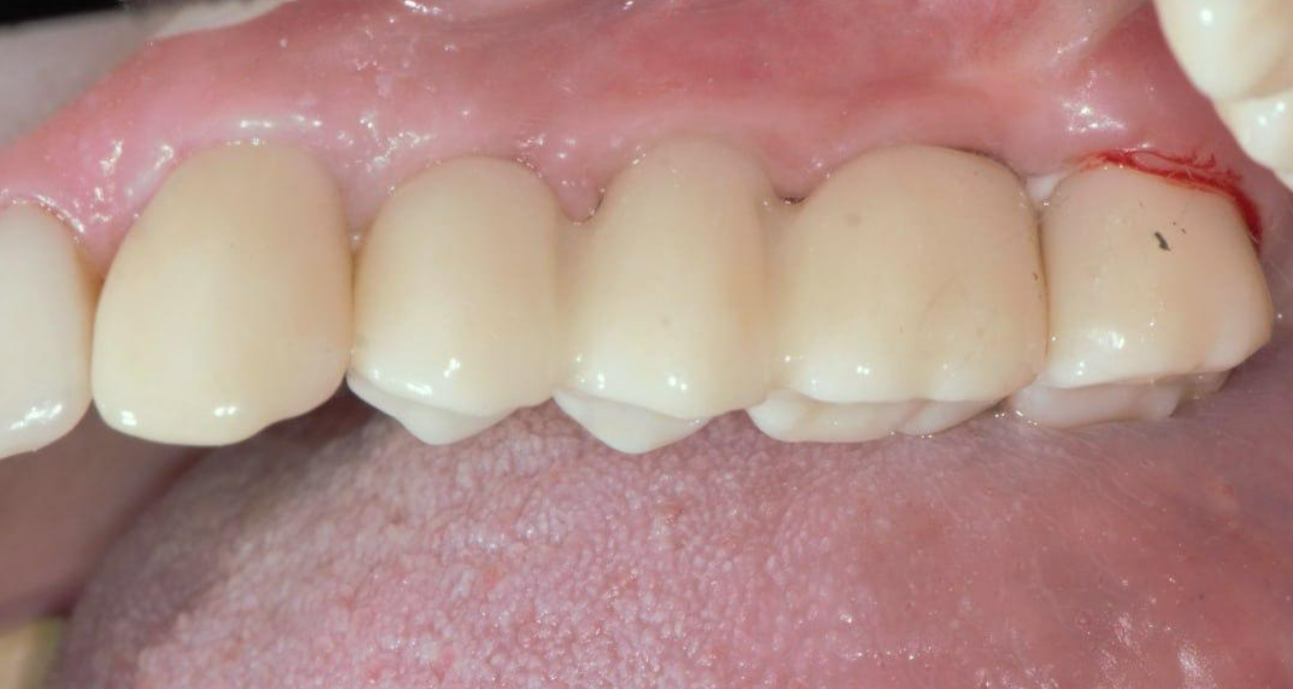

The screw-retained zirconia bridge and the crowns on teeth 13 and 17 show a precise fit, as seen in the photo below.

The completed restoration, with sealed screw access holes, is aesthetically pleasing and anatomically correct. Masticatory function is fully restored, and the patient is completely satisfied with the result.

The gingival contour around the prosthesis is well-defined; the papillae completely fill the embrasures, and a band of attached keratinized gingiva is clearly visualized and anatomically correct.